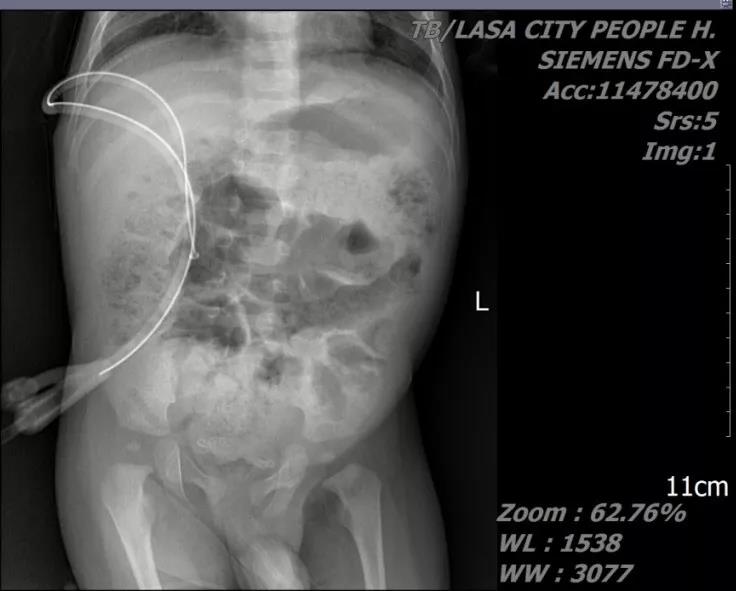

患儿,男,1岁10个月,主因“腹痛腹胀伴排尿困难1天”就诊。术前诊断:1.尿道结石;2.右输尿管结石;3.双肾结石。急诊一期予以经由尿道结石碎石术+右输尿管结石碎石术+双侧输尿管结石支架置入术。二期行mPCNL。

术后患儿愈合良好,术后第3天第4天依次拔除肾造瘘管,第5天拔除尿管出院。